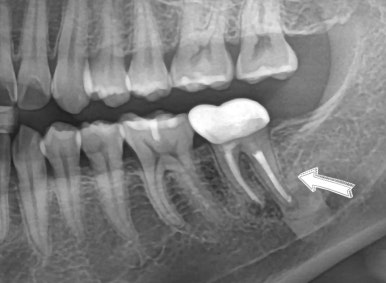

🦷 보철 단계 (3개월 후)

임플란트 식립 후

👉 3개월 동안 골유착을 기다립니다.

이후

✔ ISQ 측정 (고정력 확인)

✔ 맞춤형 지대주 제작

✔ 최종 크라운 장착

✔ 적용된 보철 방식

- Custom Abutment (맞춤 지대주)

→ 음식물 끼임 최소화 - SCRP 크라운

→ 유지보수 용이 + 안정성 확보

🎯 치료 결과 (6개월 후)

✔ 임플란트 안정적 유지

✔ 통증 완전히 해소

✔ 음식물 끼임 없음

✔ 정상적인 식사 가능

👉 환자분 만족도 매우 높은 케이스였습니다 😊